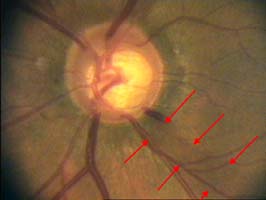

V nasálním horním kvadrantu terče vidíme obnažené cévy, které dříve probíhaly v lemu. Toto obnažení může být jedním z prvních příznaků glaukomové neuropathie.